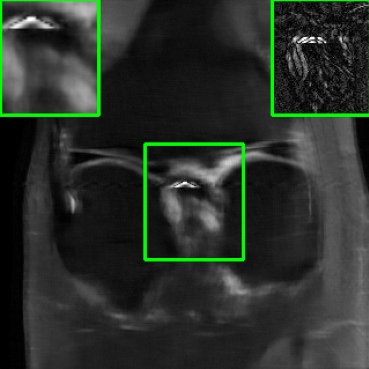

Performance on the Stanford FSE Dataset: We also performed image reconstructions with the Stanford multi-coil FSE dataset, which is a smaller dataset. We used same settings for the networks and training as in Section IV-A. Table III shows that LONDN-MRI significantly outperforms the globally learned MoDL network at both 4x and 8x acceleration. This indicates benefits for the proposed framework for smaller, more diverse datasets. Figs. 7 and 8 display visual comparisons that show the LONDN-MRI scheme recovering sharper features than the globally learned network.

| Ground Truth | Initial | Global | LONDN-MRI | LONDN-MRI | Oracle |

| (1 iteration) | (2 iterations) | ||||

![]() |

| PSNR = dB | PSNR = 22.01 dB | PSNR = 29.02 dB | PSNR = 31.46 dB | PSNR = 31.74 dB | PSNR = 31.87 dB |